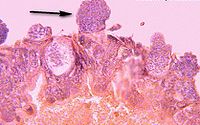

显微镜下的疟原虫

内期裂殖子呈卵圆形,有表膜复合膜(pellicular complex)包绕。大小随虫种略有不同,平均长1.5µm,平均直径1µm。

表膜(pellicle)由一质膜和两层紧贴的内膜组成。质膜厚约7.5µm,内膜厚约15µm,有膜孔。紧靠内膜的下面是一排起于顶端极环(polar ring)并向后部放散的表膜下微管(subpellicular microtubule)。内膜和表膜下微管可能起细胞骨架作用,使裂殖子有硬度。游离的裂殖子的外膜有一厚约20µm表被(surface coat)覆盖。此表被是电子致密、坚实的纤丝,在性质上似是蛋白质,可能在对宿主免疫反应的应答中起作用。在裂殖子侧面表膜有一胞口(cytostome),红细胞内期各期原虫通过胞口摄取宿主细胞浆